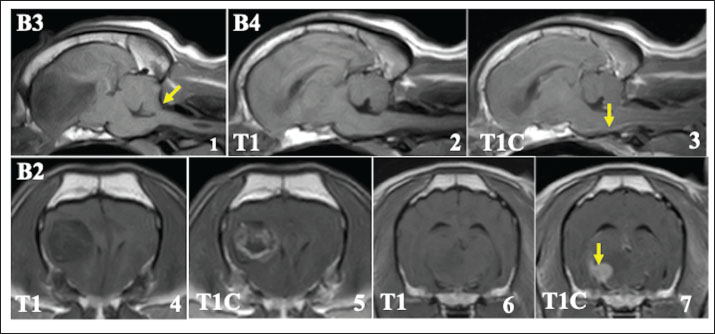

Magnetic resonance imaging of presumed glial tumors

Brain tumors in all 15 cases were present in the cerebrum and were suspected to be tumors derived from glial cells (Fig. 1). Among the 15 cases, 14 cases had a single tumor site, and one case had 2 tumor sites in the cerebrum on MRI. Furthermore, 11 of the 15 cases appeared to be in contact with the lateral ventricles, and in 3 cases, the tumor tissues seemed to invade into the lateral ventricles on MRI. Although the signal intensity on MRI of these glial tumors varied, most cases showed low to iso-signal intensity on T1-weighted images and iso- to high-signal intensity on T2-weighted images. The enhancing effect of the contrast medium also varied among the cases; one case showed a clear ring-enhancing effect, 2 cases showed homogenous enhancement (one case with a ring-shaped periphery), and 7 cases showed heterogenous enhancement (three cases with a ring-shaped periphery). The remaining 5 cases showed almost no enhancement. Cerebellar herniation, possibly induced by the intracranial tumor, was observed in two cases. Additional CT evaluations of the thoracic and abdominal cavities at the first visit showed no distant metastatic lesions and other abnormal findings in any of the patients.

Fig. 1. Typical MRI findings of the presumed glial tumors observed in this study. In many cases, brain tumors showed low signal intensity on T1-weighted images (1) and high signal intensity on T2-weighted images (2). Various enhancing effects were observed in the contrast examination, but most of them showed relatively weak enhancement (3). Some tumor tissues that clearly protruded into the ventricles were also observed (4, asterisk).